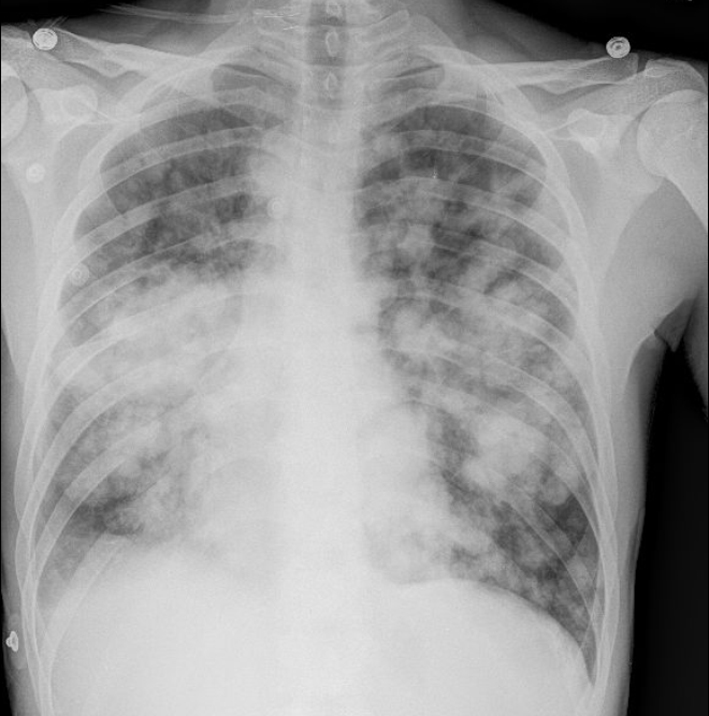

A chest X-ray (Fig. 1) was obtained and showed the presence of multifocal rounded airspace opacities within both lungs. Subsequently, a CT scan of the chest (Fig. 2, 3) was obtained which demonstrated bilateral pulmonary emboli along with bilateral conglomerate pulmonary nodules in both lower lungs.

![]() Click for large image | Figure 1. Chest X-ray showing bilateral rounded airspace opacities. |

In rare cases, patients may present with symptoms from the metastasis. In these patients, a careful physical examination is of prime importance in pointing towards the correct diagnosis. Radiological features such as multiple lung nodules greater than 1 cm in size seen on a plain chest radiograph are also usually indicative of disseminated malignancy to the lungs [5, 6]. Such large, rounded “cannonball” nodules are associated with poor prognosis [7, 8].